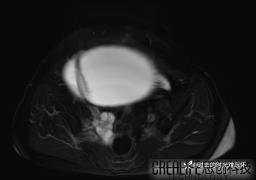

腹大能容5000液;术后腹部好轻松。妙手回春有结果。公布结果。

患者性别:女

患者年龄:65岁

主诉: 发现腹部隆起半年余。无其他明显不适。

浆液性囊腺瘤 (22)